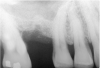

First, a periapical radiograph is taken to determine the amount of bone subantrally. It should be noted that a periapical film has an average error of 14%.23 Therefore, it is advantageous to take the radiograph in a manner that includes a marker (5-mm wide ball bearing) in order to be able to calculate the magnitude of radiographic error (Figure 1).

Figure 1  At tooth site No. 14, a periapical radiograph was taken with the long-cone paralleling technique. The radiographic ball marker measured 5.8 mm while its actual diameter is 5 mm. The enlargement is 0.8 mm, therefore the magnification error is 0.8/5 = 16%. By correcting for this error, a closer approximation of the amount of bone from the osseous crest to the sinus floor can be made.

Figure 1